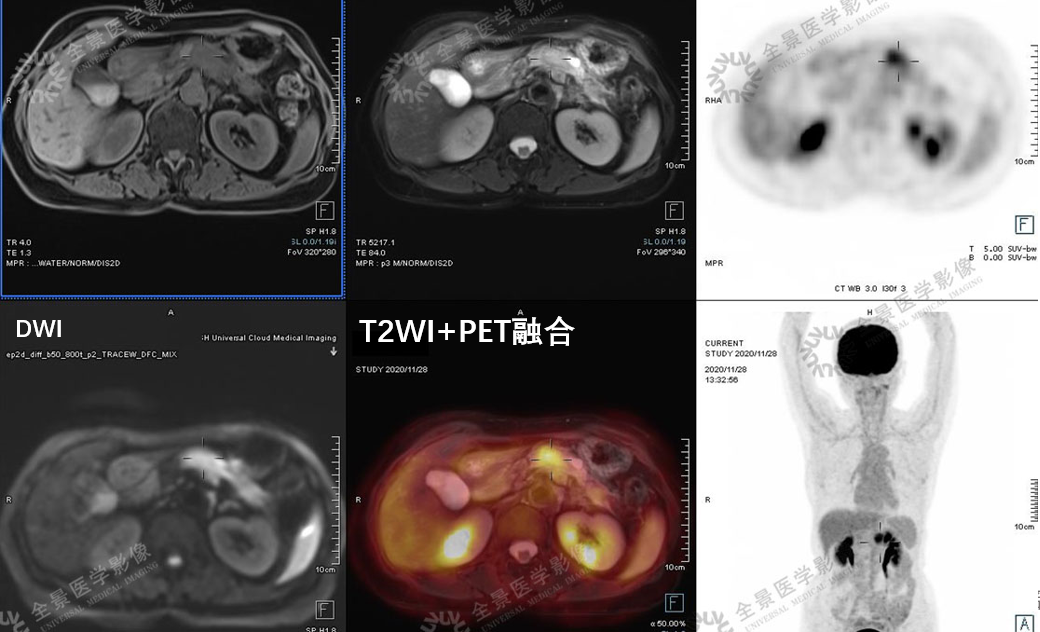

1. 胰腺占位

女 66岁 胰腺癌,PET/CT表现为FDG高代谢病变,增强MR病灶主体乏血供、低强化表现